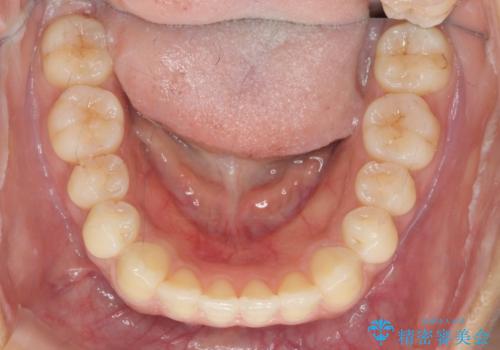

- 前歯のガタつき、上下たがい違いになっている歯並び(クロスバイト)の改善を求めて来院されました。

インビザラインによる矯正治療を行いますが、クロスバイトの改善をワイヤー部分矯正で事前に行うことにより治療期間の短縮する治療計画を立案します。

上下すれ違った噛み合わせはマウスピースでは改善に時間がかかり、またねじれが残ってしまうことも多々見られます。

マウスピース矯正を行う前に、これらの症状の改善の得意なワイヤー部分矯正を行うことで治療期間を短縮し、確実にすれ違いを改善することができます。